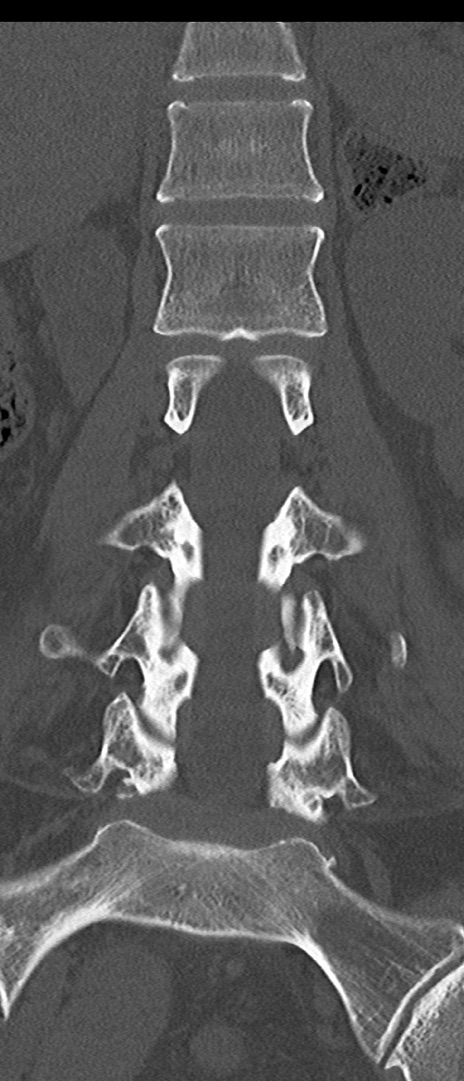

【整形】TIPS症例4 腰椎CT(冠状断像)

腰椎CT